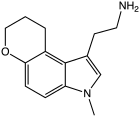

| CP-132,484 | artificial | 1-methyl-4,5-(OCH2CH2CH2) | H | H | 1-(2-aminoethyl)-3-methyl-8,9-dihydropyrano(3,2-e)indole | 143508-76-3 |